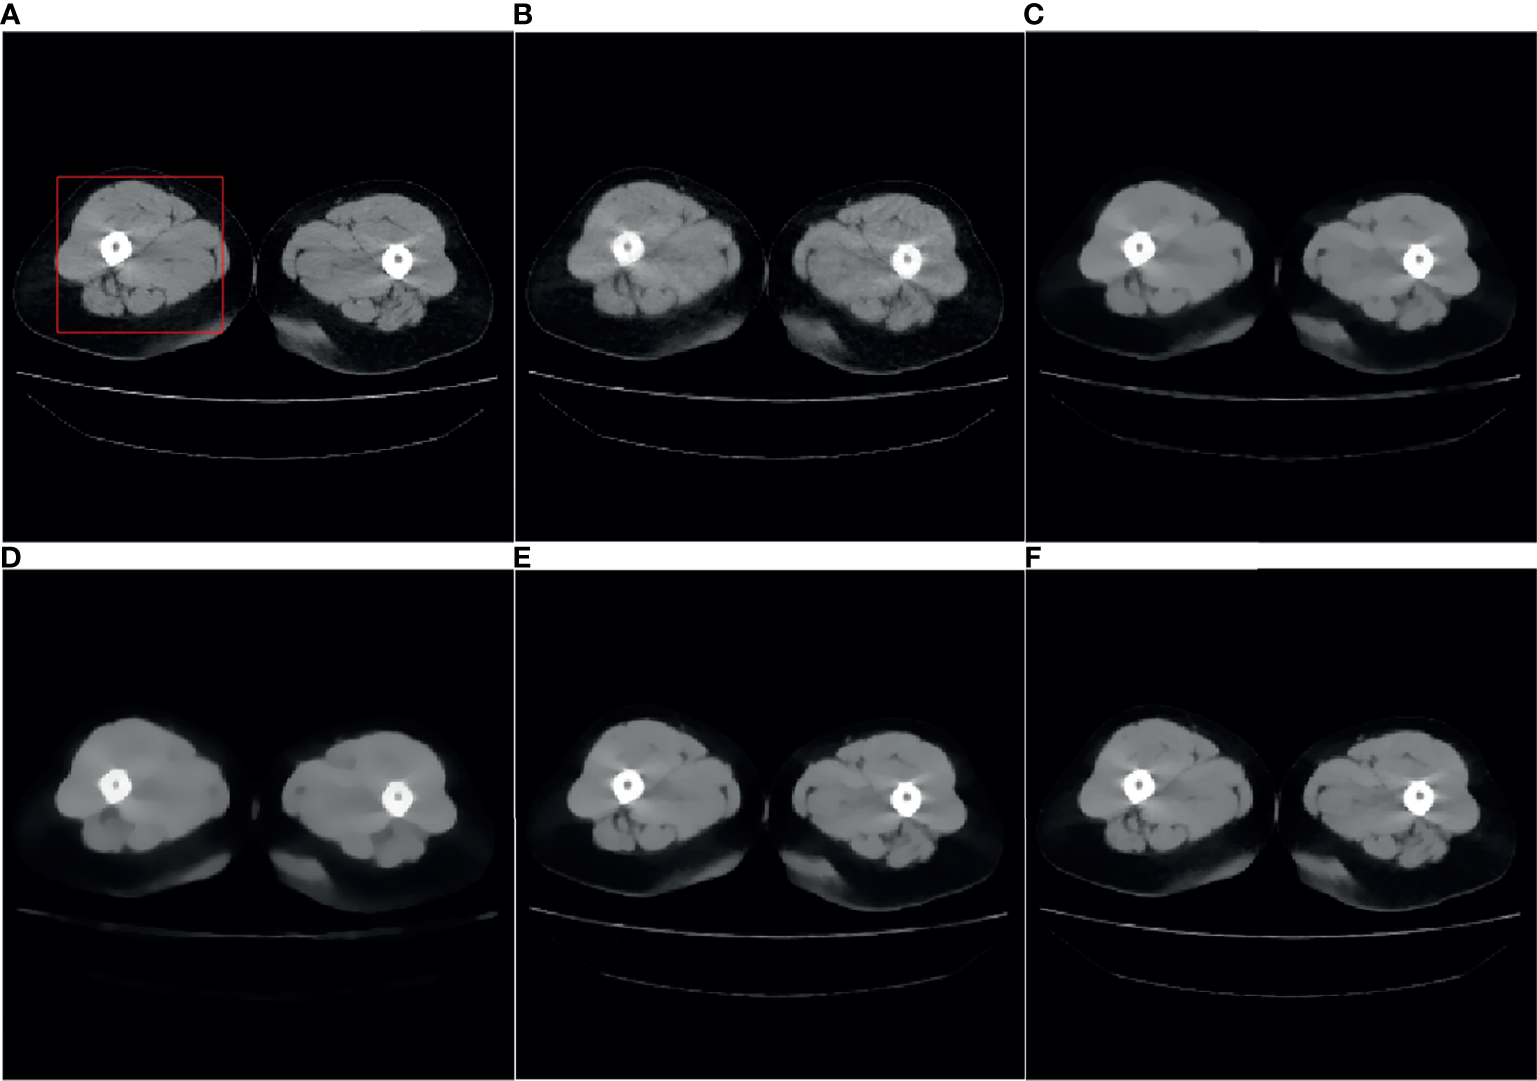

For the SART algorithm, λ is set to 1, the reduction of λ, λred is set to 0.99. For the ASD-POCS algorithm, λ is set to 1, λred is set to 0.99, TV hyperparameter α is set to 0.002. For the SART-TV algorithm, λ is set to 1, λTV is set to 15 which gives the ratio of importance of the image vs the minimum total variation. and the reconstruction result of the 80th layer of data 1 is shown in Figure 1.

Figure 1 Reference image and 32-angle reconstruction results: (A) reference image; (B) SART; (C) ASD-POCS; (D) SART-TV; (E) TpV; (F) TpV-GIF.

It can be seen from Figure 1B that the SART reconstructed image under the sparse angle is full of artifacts and the image quality is poor. The images in Figures 1C-F are relatively smooth because they all involve TV constraints. However, the TV minimization reconstruction result in Figure 1C has a step effect, and many small details are smoothed out. The image in Figure 1D is more serious in the problem of excessive smoothness and has a strong sense of smearing. The image reconstructed based on TpV minimization is much better, suppresses artifacts while retaining most of the edges and details, and the reconstruction results of the algorithm proposed in this paper show better edge retention characteristics. In order to better observe the reconstruction details, the part of the image in the red box in Figure 1 is individually enlarged and displayed to Figure 2. As shown in Figure 2, our algorithm can effectively remove artifacts while better restoring the edges and details of the image. Figure 3 is a profile graph. It can be seen that the reconstruction result of TpV-GIF is very close to the reference image, no matter in a smoother area or an edge area where the voxel value changes greatly. This means that the algorithm has a good performance in suppressing noise and preserving edge details.

Figure 2 ROI area enlargement result: (A) real graphics; (B) SART; (C) ASD-POCS; (D) SART-TV; (E) TpV; (F) TpV-GIF.